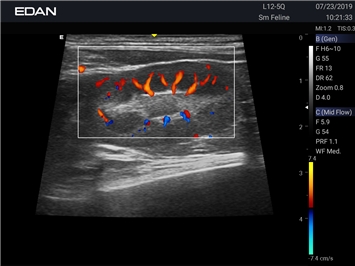

Ветеринарный ультразвук одним нажатием. Система Acclarix AX2 VET разработана с целью обеспечить бескомпромиссную производительность по доступной цене. Наличие уникальных двойных аккумуляторов в легком корпусе массой 4,5 кг из магниевого сплава позволяет системе Acclarix AX2 VET удовлетворять все потребности ветеринарных исследований, сохранив низкую стоимость.

EDAN Acclarix AX2 VET представляет собой специализированную ветеринарную ультразвуковую систему, сочетающую высокую производительность с доступной ценой. Благодаря продуманной конструкции и передовым технологиям, система обеспечивает качественную диагностику животных различных видов.

Цветовой допплер:

Да

Энергетический допплер:

Направленный энергетический допплер: